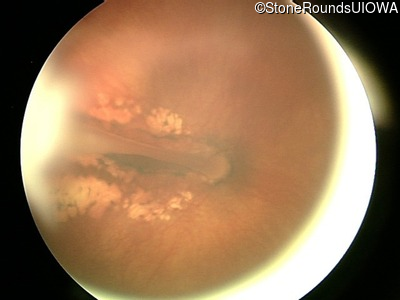

Visit at age: 13 years

Fundus Photography - Right - 20/250

Exemplar